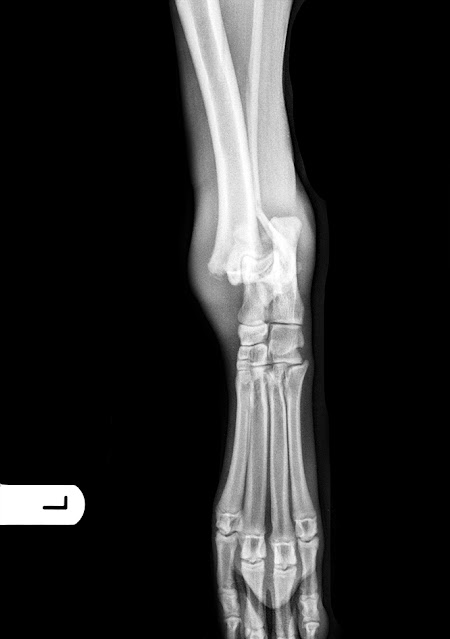

Fractura fisis distal

tibia, Salter Harris tipo II

Como ya se ha comentado, se

trata de una fractura de la fisis distal de la tibia izquierda, Salter Harris

tipo II. En este tipo de fracturas el espacio para colocar implantes es mínimo

a nivel distal, por lo tanto no es fácil poner una placa de osteosíntesis y

todos los autores coinciden en que la resolución más adecuada es mediante

agujas de Kirschner.

Al principio puede resultar

extraño resolver una fractura en un perro de 25 kg, muy activo, y que sigue

creciendo, sólo con agujas, pero es cuestión de poner varias agujas, y mantener

al paciente encerrado en una jaula, para evitar ejercicios bruscos en fases

tempranas del proceso de cicatrización.